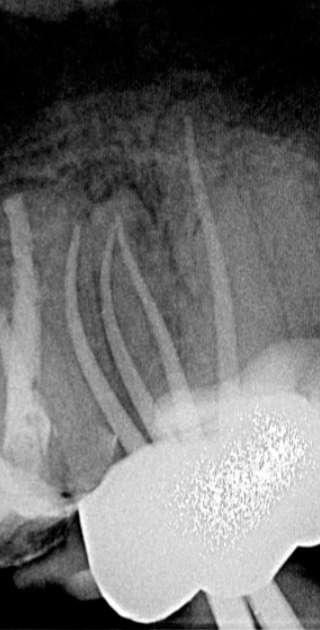

Röntgenologischer Befund:

Das präoperativ angefertigte Röntgenbild (Abbildung 10) zeigt den bereits vom Vorbehandler trepanierten Zahn 27. Die Wurzelfüllung erscheint inhomogen. Das Wurzelfüllmaterial im mesiobukkalen Kanal ist über den röntgenologischen Apex hinaus extendiert und es zeigt sich eine periapikale Osteolyse der mesiobukkalen Wurzel.

Abbildung 10: Präoperative diagnostische Aufnahme